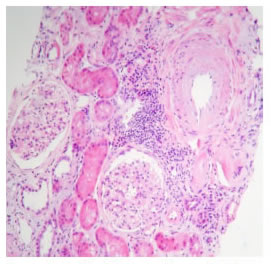

Es interesante observar el trasfondo de las pérdidas de los injertos y los rechazos agudos. Ninguna pérdida del injerto renal se asoció con rechazo crónico; por el contrario, se relacionaron con recurrencias de la enfermedad de base, como se evidenció en la histopatología (figuras 4 y 5). En los casos de rechazo del injerto, el rechazo clínico coincidió con falta de cumplimiento del tratamiento. Además, 15 pacientes suspendieron o disminuyeron la dosis de alguno de los inmunosupresores y no presentaron pérdida del injerto o rechazo agudo del trasplante. Estos hallazgos podrían sustentar la hipótesis del bajo riesgo inmunológico que presenta este grupo de pacientes, en quienes, en teoría, se requiere una menor dosis de inmunosupresores, en comparación con el grupo de trasplantes con HLA no idéntico; por lo tanto, se podrían evitar efectos secundarios como toxicidad por el fármaco, predisposición a infecciones, propiedades cancerígenas, riesgo de diabetes mellitus, hiperlipemia e hipertensión arterial sistémica, alteraciones hematológicas o enfermedades óseas, entre otros 6,13,26,28.